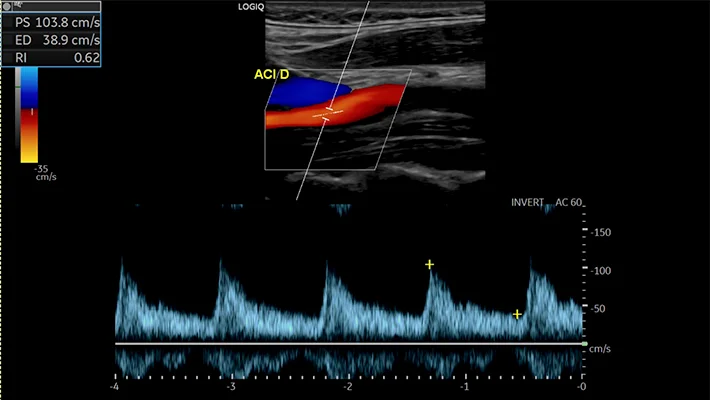

- дуплексным — сочетает изображение сосуда с анализом скорости и направления кровотока;

- триплексным — дополняет картину цветным отображением кровотока, что облегчает оценку сужений и деформаций.

- гемодинамические характеристики: скорость, направление и равномерность кровотока;

Заключение содержит описание состояния сосудов и объективные количественные показатели (скорость кровотока, степень стеноза, толщина КИМ). Оно не является диагнозом, а используется лечащим врачом — неврологом, терапевтом или сосудистым хирургом — для уточнения причин симптомов и выбора тактики лечения.